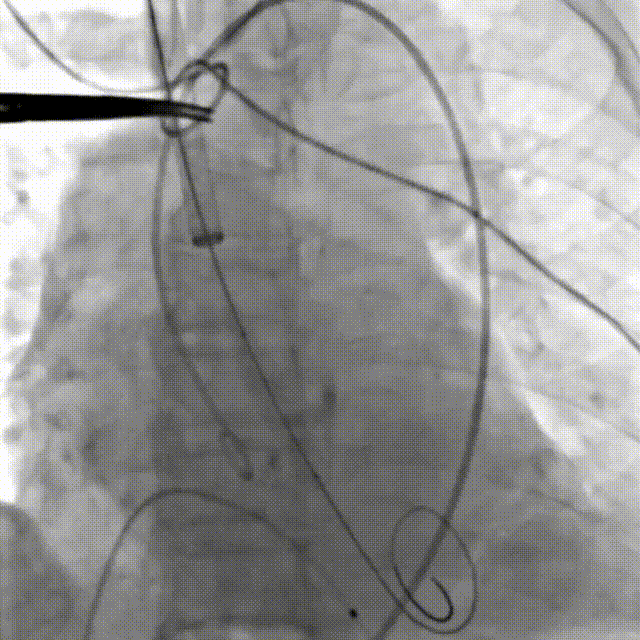

患者全麻后,游离颈动脉建立入路,主动脉根部造影显示主动脉瓣明显钙化伴重度狭窄。直头导丝跨瓣后,测得左心室、主动脉压力分别为180/-7mmHg,84/45mmHg。在180次/分快速心室起搏下,选择18mm球囊进行预扩张。根据术前评估及球囊预扩情况,最终选择23mm Prizvalve®球扩瓣进行植入,主动脉根部造影见轻微主动脉瓣反流,复查左心室、主动脉压力分别为151/1mmHg、150/72mmHg。术后即刻经食道超声心动图评估峰值流速1.4m/s,平均压差4mmHg,瓣口面积约2.1cm²,血流动力学指标理想。

释放后造影